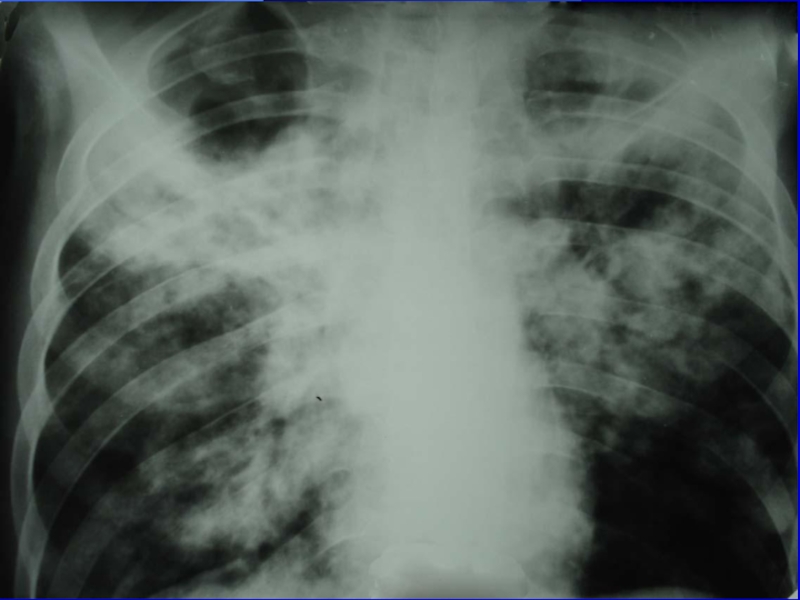

Рентгенологическая картина острого милиарного туберкулеза

легких в первые дни заболевания характеризуется диффузным понижением прозрачности легочных

полей, а затем появляются симметрично множественные округлой формы нерезко очерченные очаги, величиной до просяного зерна.

характеризуется наличием мелких мягких очагов

(1-2 мм) одинаковой величины, расположенных симметрично в над- и подключичных

зонах, преимущественно в кортикальных слоях легких (эксудативного характера).